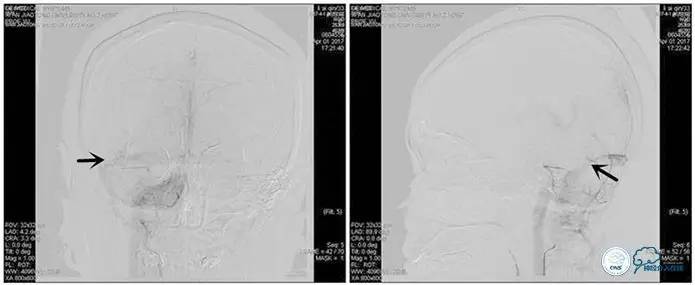

右侧ICA正位

右侧ICA侧位

术中造影

5ml/s,总量8ml,压力100~150